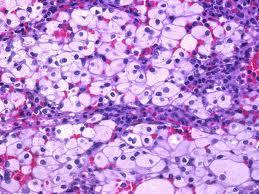

Enfermedad de Gaucher. Los individuos afectados presentan hepatoesplenomegalia y células características, cargadas de lípidos, en distintos tejidos y en la médula ósea. En el tipo más frecuente de esta enfermedad no hay compromiso de sistema nervioso. Se acumulan en las células glucocerebrósidos, no degradados por la falta de glucocerebrosidasa.